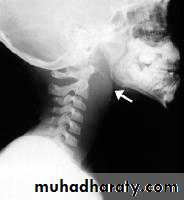

• Haematological: CBP---- hypochromic microcytic anaemia, low serum iron and high iron binding capacity.• Ba-swallow: web at the postcricoid region.

Lateral X-ray of the neck, which shows increase in prevertebral soft tissue shadow or an air-fluid level.

Lateral X-ray of the neck shows evidence of bone destruction and loss of the normal curvature of the cervical spine.Treatment